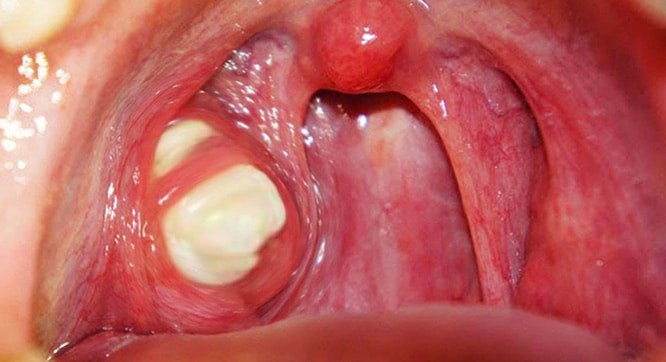

Bademcik taşları bademciklerin üzerinde veya içinde gelişen sarı ya da beyaz renkli oluşumlardır. Varlıkları fark edilmeyebilir ve boyutları (pirinç ya da üzüm kadar) farklılık gösterebilir. Bazen bademciklerin şişmesine neden olabilecek kadar büyük oluşumlara dönüşebilir. Yetişkinlerde çocuklardan daha sık görülür.

Bademcik taşları ölü hücrelerin, balgam, tükürük, sümük ve yiyecek gibi farklı türdeki döküntülerin yarık, tünel ve çukurlardan oluşan bademciklerdeki kriptlere sıkışıp zamanla birikmesiyle gelişir. Potansiyel nedenleri kötü diş hijyeni, büyük bademcikler, kronik sinüs sorunları ve bademcik iltihabıdır.

Küçük bademcik taşları daha yaygındır ve herhangi bir belirti göstermeyebilir.